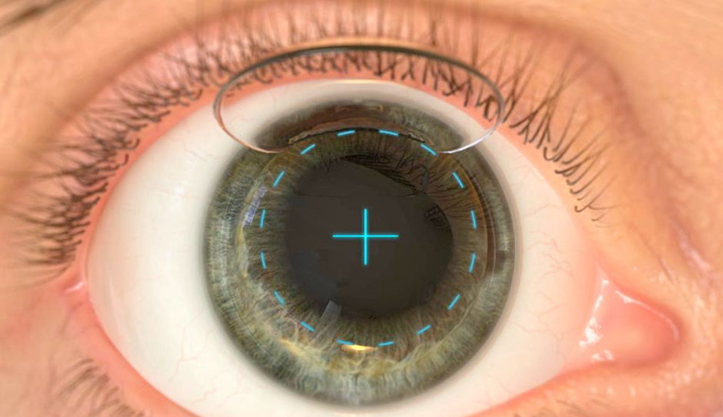

La cirugía refractiva constituye el avance tecnológico más impresionante de la medicina oftalmológica de los últimos años. La cirugía refractiva con láser, ya sea el LASIK o el PRK, actúa remodelando la superficie corneana, permitiendo neutralizar el vicio visual (miopía, hipermetropía o astigmatismo). Existen varios requisitos clínicos para postular a este seguro y eficaz procedimiento: